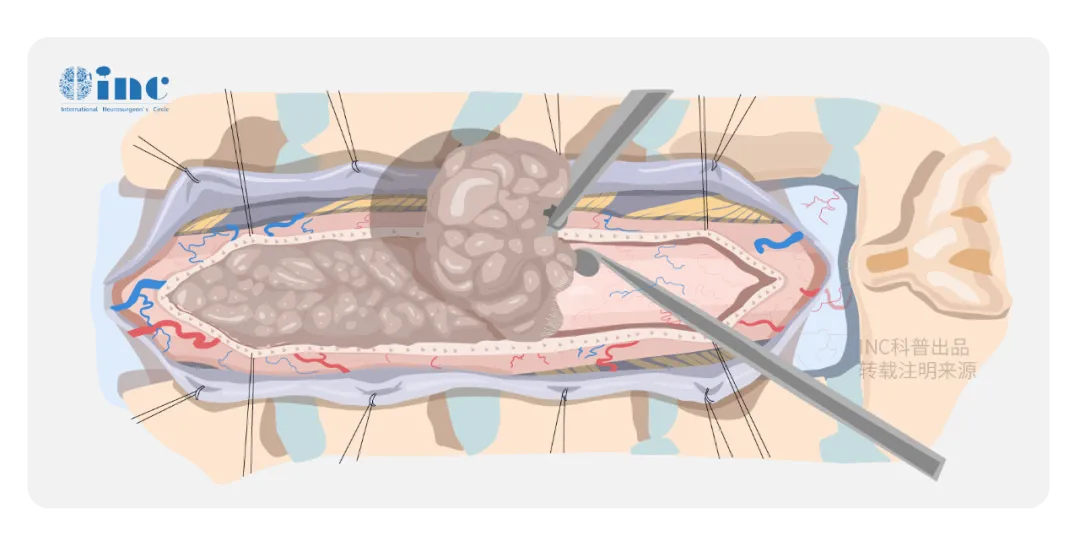

脊髓作為連接大腦與周?chē)窠?jīng)系統(tǒng)的主要通路,密布31個(gè)脊髓神經(jīng)節(jié)和來(lái)自腦干的四條運(yùn)動(dòng)神經(jīng)束。而如果腫瘤生長(zhǎng)在脊髓內(nèi),位置處于外科手術(shù)的“禁區(qū)”:所在區(qū)域部位深、被脊骨包圍、暴露困難,脊髓是很嬌嫩的組織,稍受擠壓或碰撞,即可造成永久性的障礙,下肢癱瘓、大小便失禁等。如果兩側(cè)的神經(jīng)根如果出現(xiàn)破損,病人也可能出現(xiàn)癱瘓。手術(shù)后可能會(huì)癱瘓是根植在每一個(gè)罹患脊髓髓內(nèi)腫瘤患者心中深處的恐懼。

對(duì)于原發(fā)的脊髓髓內(nèi)腫瘤,優(yōu)選手術(shù)治療。手術(shù)不僅是為了獲得病理組織學(xué)診斷,也是為了對(duì)神經(jīng)組織進(jìn)行減壓。在可能的情況下,盡可能切除腫瘤。手術(shù)主要的目的是脊髓功能保護(hù)與恢復(fù),在保護(hù)脊髓功能的前提下,分離腫瘤-脊髓界面盡量全切腫瘤。

手術(shù)中怎么辦才能避免對(duì)脊髓的損傷嗎?

電生理監(jiān)測(cè)可在諸多方面有助于神經(jīng)外科醫(yī)生的判斷。每例脊髓腫瘤手術(shù)均應(yīng)進(jìn)行持續(xù)同步的術(shù)中感覺(jué)誘發(fā)電位(SEPs)和MEPs監(jiān)測(cè),并由專(zhuān)職的神經(jīng)生理學(xué)家操作。第一,使醫(yī)生易于鑒別神經(jīng)結(jié)構(gòu),特別是對(duì)于那些因腫瘤、外傷或以前的手術(shù)已使脊髓結(jié)構(gòu)發(fā)生改變的病例;第二,可指導(dǎo)手術(shù)切除病變的程度和范圍,以便保護(hù)神經(jīng)功能;第三,可有助于確定病變?cè)趥鲗?dǎo)功能受損神經(jīng)上的解剖定位。

“根據(jù)我的手術(shù)經(jīng)驗(yàn),在保留腦干和脊髓中運(yùn)動(dòng)感覺(jué)神經(jīng)功能的前提下,手術(shù)是可行的。手術(shù)中必須要有電生理監(jiān)測(cè)。”